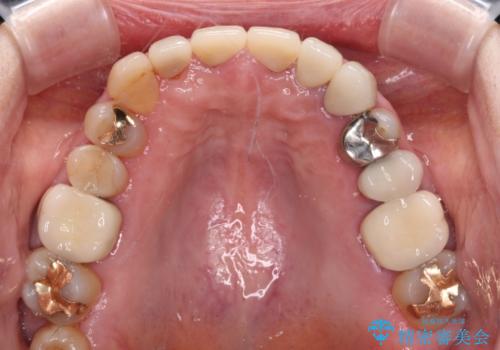

外れてしまったクラウンを保管しておき、新しいクラウン製作の際に技工所に送ることで、今までと同じような色合いに仕上げることができ、周囲のクラウンとバランスを取ることができます。